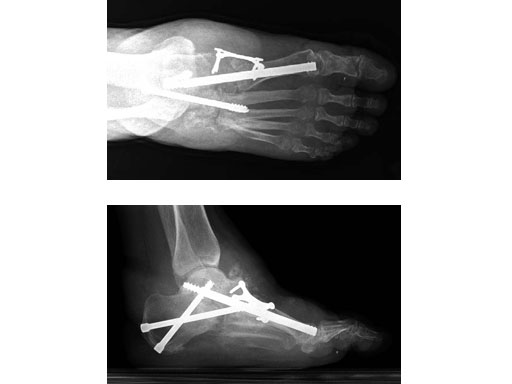

Case 1: 47-year-old female

Case provided by Andrew K Sands, New York, USA

Charcot foot treated with MFB and X-plate